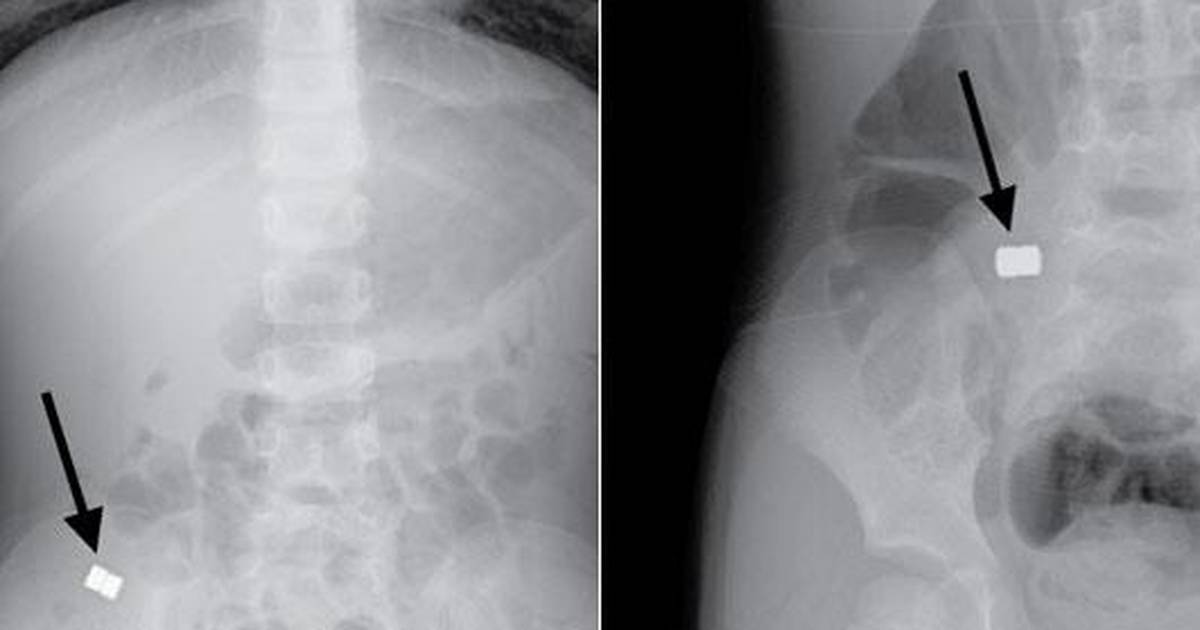

Ребенок проглотил или нет